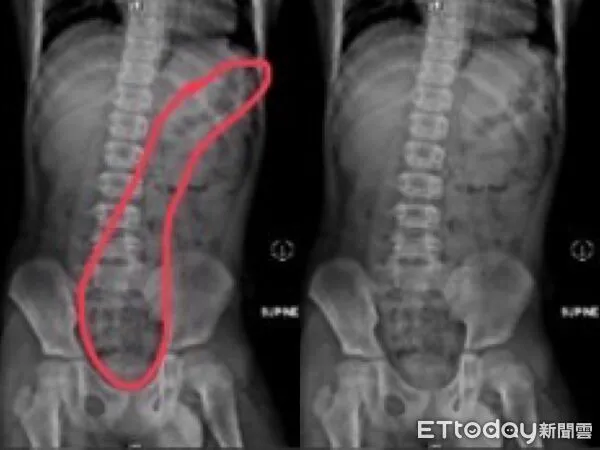

收治病例的阮綜合醫院急診兒科主治醫師蕭宇超分享,近期急診出現多例兒童便秘案例,一名11歲小五男童被送到急診時,嘴唇嚴重發紫、手腳冰冷狂冒冷汗,男童狂喊肚子痛,經問診、觸診及腹部X光檢查後診斷是嚴重便秘,積糞都快塞到胸部位置去,經過灌腸後,男童解出很多大便,症狀也隨即緩解。媽媽說,男孩習慣邊大便、邊玩手機,都是被罵上太久才匆忙沖馬桶、從廁所出來,自己也都不清楚是否有大出來或有沒大乾淨。